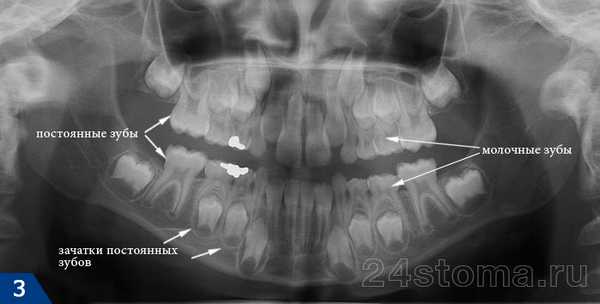

На рис.2 вы можете увидеть - как рентгеновском снимке выглядит смена молочных зубов у детей на постоянные. В данном случае мы видим, что у ребенка уже прорезались постоянные центральные и боковые резцы, а также первые постоянные моляры. Но в боковых отделах челюстей мы также видим еще сохранившиеся молочные зубы, между корнями которых расположены зачатки постоянных зубов.